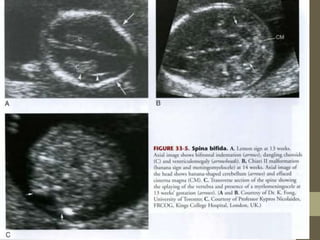

Chiari II Malformations

โ€ข See in 95% of Myelomenigoceles

โ€ข Abnormalities Include:

โ€ข 1. Caudal displacement of

โ€ข CEREBULLUM

โ€ข Pons

โ€ข Medulla

โ€ข 2. 4th Ventricle Elongated

โ€ข 3. Posterior Fossa small

โ€ข 4. Beaking of Tectum

โ€ข 4. Cisterna Magna

โ€ข Obliterated

Spina Bifida

โ€ข Most Common: Lumbosacral

โ€ข Can occur anywhere in spine

โ€ข US Findings:

โ€ข Outward Splaying of Laminae

โ€ข Soft Tissue Defect

โ€ข overlies bony defect

โ€ข Protruding Sac (+/- neural tissue)

โ€ข +/- Chiari II Malformation

โ€ข +/- Ventriculomegaly (75%)

โ€ข Banana Sign

โ€ข Cerebellar hemispheres squashed

into shape banana

โ€ข Cisterna Magna is small or gone

โ€ข Lemon Sign

โ€ข Bossing of frontal bones

โ€ข Lemon shaped head on axial scan